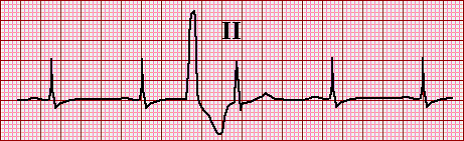

Single lead electrocardiogram (ECG) showing a ventricular premature beat (VPB)

fully compensated because these two normal ones are the same distance as the three previous normal ones

single pvc with full compensatory pause